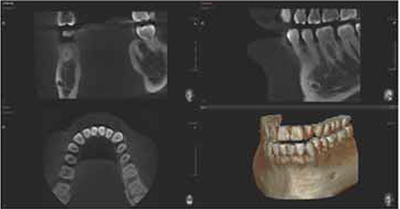

5X5 scans are useful for a specific area diagnosis with minimum X-ray exposure for patients. It can especially increase the accuracy of endodontic diagnosis by exactly checking the amount of root canals and abnormal root canal shapes such as C-shapes that are difficult to check using a 2D X-ray system.